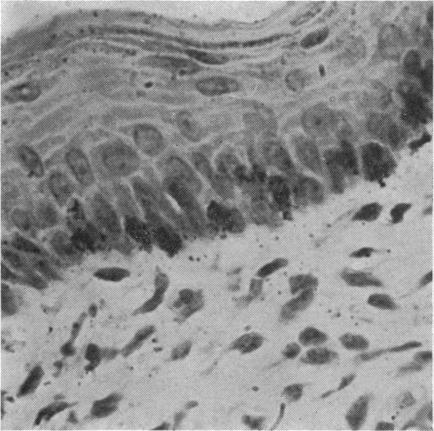

The morphology of the keratinizing epithelia in the mouth is reviwed in the light of recent knowledge. There appears to be a spectrum of degrees of keratinization rather than distinct types, and a degree of keratinization is reflected in the degree of packing and orientation of tonofilaments. The role of keratohyaline and other granules in the process is discussed and it is suggested that modification of the cell membrane is an important part of keratinization. Although the potential of the various areas in the mucosa is genetically determined and appears early in fetal life, the connective tissue exerts an influence on the extent of keratinization of the surface in a manner which is not understood.

根据最新知识,对口腔中角化上皮的形态进行了综述。角化程度似乎存在一个连续谱,而非不同类型,角蛋白丝的聚集和排列程度反映了角化程度。文中讨论了透明角质颗粒及其他颗粒在此过程中的作用,并提出细胞膜的修饰是角化的重要组成部分。尽管黏膜各区域的潜能由基因决定且在胎儿期早期就已显现,但结缔组织以一种尚不清楚的方式影响着表面的角化程度。